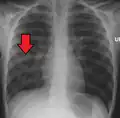

![]() | |

| Chest X-ray of a pneumonia caused by influenza and Haemophilus influenzae, with patchy consolidations, mainly in the right upper lobe (arrow) | |

X-ray presentations of pneumonia may be classified as lobar pneumonia, bronchopneumonia, lobular pneumonia, and interstitial pneumonia.[75] Bacterial, community-acquired pneumonia classically show lung consolidation of one lung segmental lobe, which is known as lobar pneumonia.[42] However, findings may vary, and other patterns are common in other types of pneumonia.[42] Aspiration pneumonia may present with bilateral opacities primarily in the bases of the lungs and on the right side.[42] Radiographs of viral pneumonia may appear normal, appear hyper-inflated, have bilateral patchy areas, or present similar to bacterial pneumonia with lobar consolidation.[42] Radiologic findings may not be present in the early stages of the disease, especially in the presence of dehydration, or may be difficult to interpret in the obese or those with a history of lung disease.[24] Complications such as pleural effusion may also be found on chest radiographs. Laterolateral chest radiographs can increase the diagnostic accuracy of lung consolidation and pleural effusion.[41]